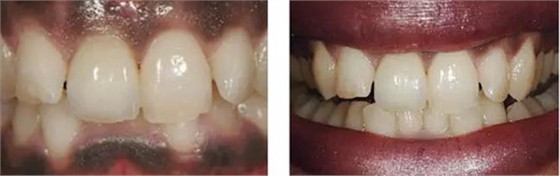

圖10、剛植入種植體當(dāng)天的情況(左)和植入種植體1年時的情況(右)。

圖11、牙冠戴入1個月以后。軟組織外形良好,形成了良好的弧線形牙齦形態(tài)而沒有瘢痕。保持了原有的色素沉著的顏色和形狀。

圖12、種植術(shù)后1年顯示良好的美學(xué)效果。